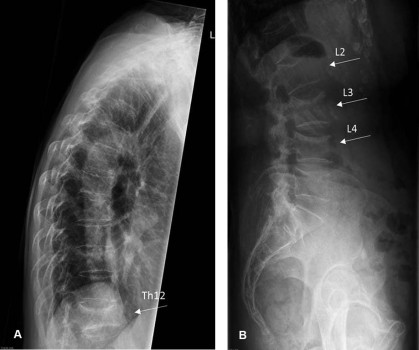

Een 71-jarige vrouw met primaire osteoporose en een klinische wervelinzakkingsfractuur van de tweede lendenwervel wordt vanaf 2012 vijf jaar lang behandeld met denosumab omdat zij orale bisfosfonaten niet verdraagt. Eind 2017 stopt zij met denosumab omdat het fractuurrisico als laag wordt ingeschat. De botmineraaldichtheid (BMD) van de heuphals en de lumbale wervelkolom (LWK) is verbeterd ten opzichte van 2012 en de T-score van heuphals en LWK is –2,0, wat erop wijst dat er geen sprake meer is van osteoporose. Uit de vertebral fracture assessment met dual-energy x-ray absorptiometrie (DEXA-VFA) blijkt dat zich geen nieuwe wervelfractuur heeft ontwikkeld [figuur 1].

In 2018, acht maanden na de laatste denosumabinjectie, bezoekt patiënte haar huisarts vanwege acute pijn in de rug, ontstaan tijdens een wandeling met een lichte rugzak. Omdat de pijnklachten aanhouden, laat de huisarts een röntgenfoto van de thoracale en lumbale wervelkolom maken. Daarop zijn inzakkingsfracturen te zien van de wervellichamen Th12, L2, L3 en L4. De fracturen van Th12, L3 en L4 waren op de opnames uit 2017 nog niet aanwezig [figuur 2].